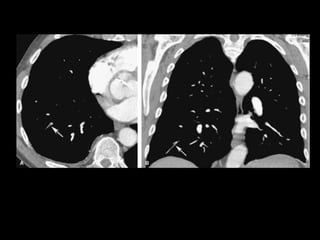

Edema intersticial pulmonar por I.C.

Edema intersticial pulmonar em TCAR.

Edema intersticial na região superior do

pulmão Dir.